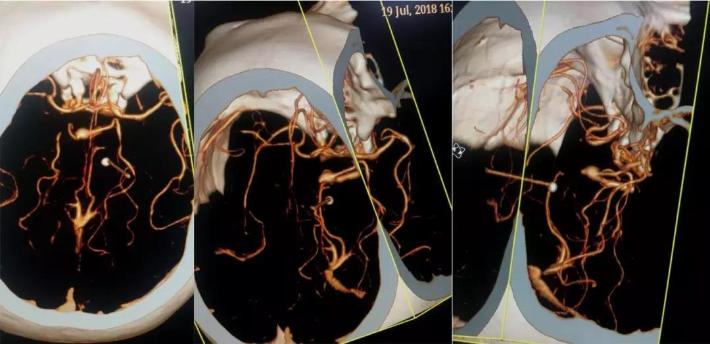

行头颈动脉CTA检查

DSA

右侧颈内动脉虹吸段夹层动脉瘤,右侧大脑前动脉A1段纤细